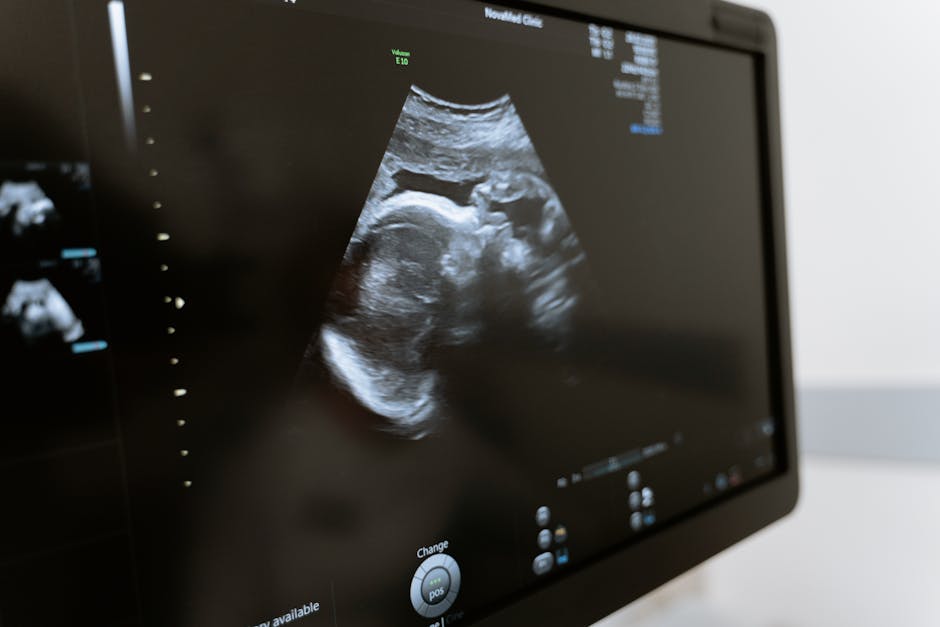

배란일 검사는 산부인과에서 시행되며, 주로 여성의 생리주기를 토대로 여러 가지 방법을 사용하여 시행됩니다. 일반적으로 배란 지표로는 체온, 경관 및 건조도 검사, 배란 테스트 키트 등이 사용됩니다. 또한, 혈청 내 여성 호르몬 수준을 측정하여 생식 호르몬의 변동을 파악하기도 합니다.